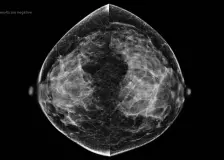

Father claims court ignored autism diagnosis in ruling on 11-year-old son’s sex change A father in Iceland is speaking out after a court allegedly stripped him of his parental rights, despite finding both parents fit, based on his disapproval of his child's sex reassignment. (Alex Koch / Fox News Digital) AI Strategy Could Eliminate Radiologist Review of Low-Risk Mammograms (MedPage Today) -- Artificial intelligence (AI) could potentially be used to safely exclude low-risk mammograms from radiologist review, according to results from a prospective noninferiority trial. When comparing standard double-blind reading... Freaked out by the news? Tips for staying calm from ex-refugees, hostages and 'uncertainty experts' Practical advice from neuroscientists and 'uncertainty experts' on how you can reduce anxiety and build resilience. Genetic risk for Alzheimer's disease may be modified by higher meat intake Older people with a genetic risk of Alzheimer's disease did not experience the expected increase in cognitive decline and dementia risk if they consumed relatively large amounts of meat. Cardiologists Reveal the No. 1 Habit to Start in Your 30s for Lifelong Heart Health New cholesterol guidelines emphasize the impact of healthy choices earlier in life. Here's how to improve heart health in your 30s, according to cardiologists. |